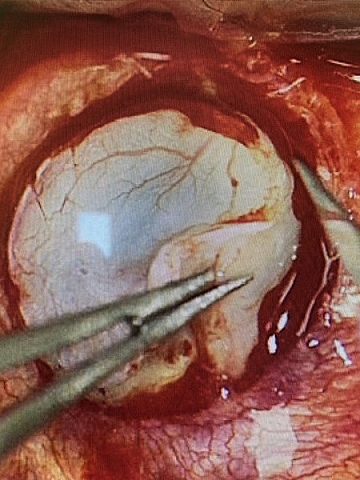

W zeszły piątek (11 czerwca 2021 r.) zespół pod kierunkiem prof. Edwarda Wylęgały, kierownika Katedry i Oddziały Klinicznego Okulistyki Śląskiego Uniwersytetu Medycznego Wydziału Nauk Medycznych w Zabrzu, wykonał zabieg wszczepienia sztucznej rogówki oraz usunięcia zaćmy w lewym oku.

Keratoproteza jest montowana w tkance rogówkowej. Jest wykonana z tworzywa o odpowiednich właściwościach optycznych, co pozwala ominąć problemy związane z utrzymaniem przezroczystości klasycznego przeszczepu rogówki od zmarłego dawcy.